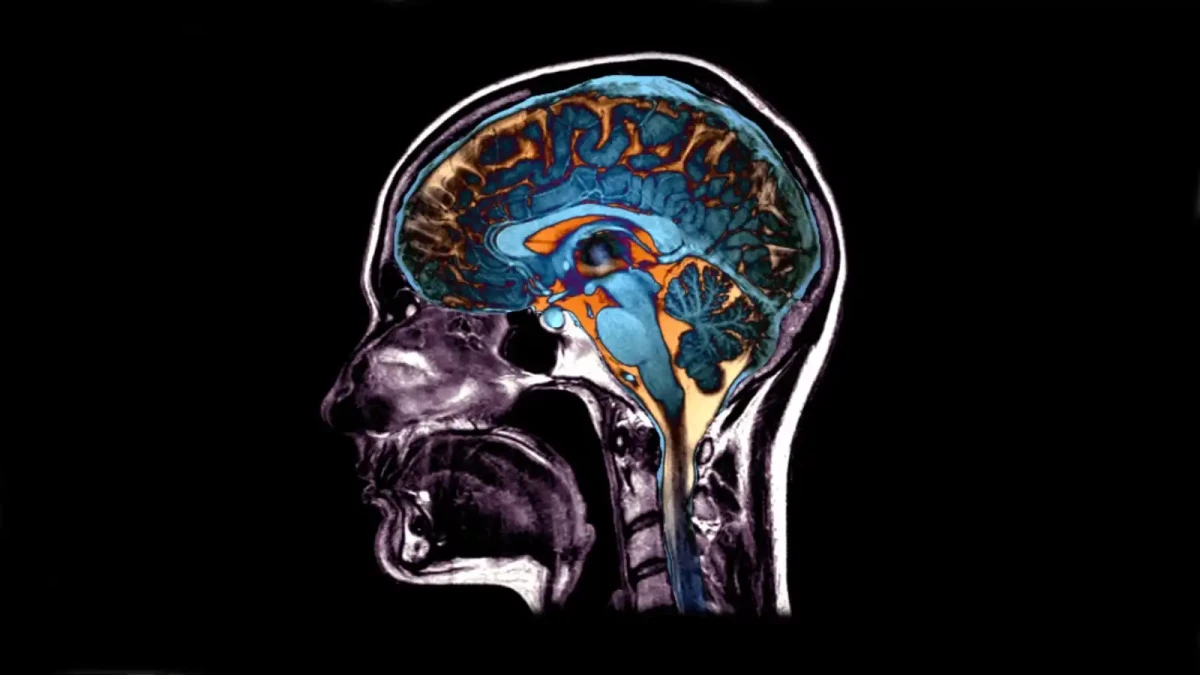

Stárnutí je proces, kterému se nevyhne nikdo z nás. Stárne však nejen naše kůže, vlasy a další viditelné části našeho těla. S postupem času stárne i náš mozek. A to i anatomicky. Dá se říct, že i našemu mozku přibývají vrásky. To, jak rychle stárneme však můžeme sami z velké části ovlivnit.

Ukázalo se, že veškeré MRI skeny mozku vykazují pět základní vzorců mozkové atrofie. Některé vzorce jsou spojeny se vznikem Parkinsonovy a Alzheimerovy choroby, které výrazně ovlivňují kognitivní schopnosti lidí. Jedna kombinace vzorů byla navíc spojena přímo s rychlejší úmrtností lidí.